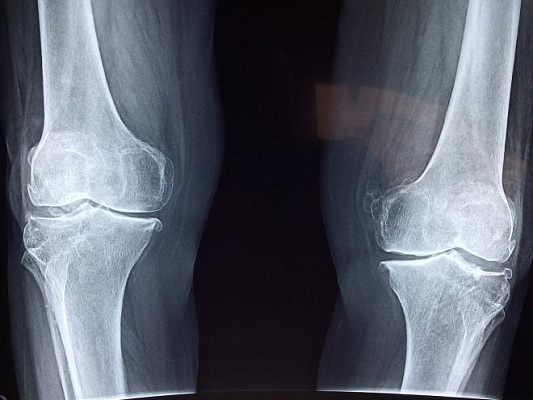

Колье и его коллеги проанализировали уникальное собрание рентгеновских снимков, сделанных в ходе исследования, которое проводилось с участием здоровых детей из Кливленда с 1926-го по 1942-й годы. Несмотря на то, что исследование дало ценную информацию о скелетном росте и развитии детей, повторить его сегодня невозможно по этическим причинам – риски радиации признаны повсеместно (в оригинальном исследовании здоровые дети проходили рентген ежегодно). Однако полученные тогда результаты позволили современным ученым идентифицировать доброкачественные опухоли костей и их последствия спустя несколько лет наблюдений.

Всего в распоряжении Колье оказались 25 555 снимков 262 детей, за которыми наблюдали в детском и подростковом возрасте. У 33 детей было обнаружено 35 доброкачественных новообразований костей (18,9%), при этом рентгеновскому облучению подвергалась только левая сторона тела. Более половины опухолей относились к неоссифицирующим фибромам (скопление соединительной ткани, которая не затвердела до состояния кости) – чаще всего они возникают в возрасте 5 лет, второй пик приходится на период скелетной зрелости, что, вероятно, связано с изменениями в темпах роста. 7 из 19 обнаруженных фибром исчезли со временем самостоятельно, другие, скорее всего, тоже «рассосались», но подтверждения этого не сохранились. Менее распространенные доброкачественные опухоли, включая эностоз, иногда именуемый «костным островком», остеохондрому и энхондрому, наблюдались на снимках на протяжении всего периода исследования.